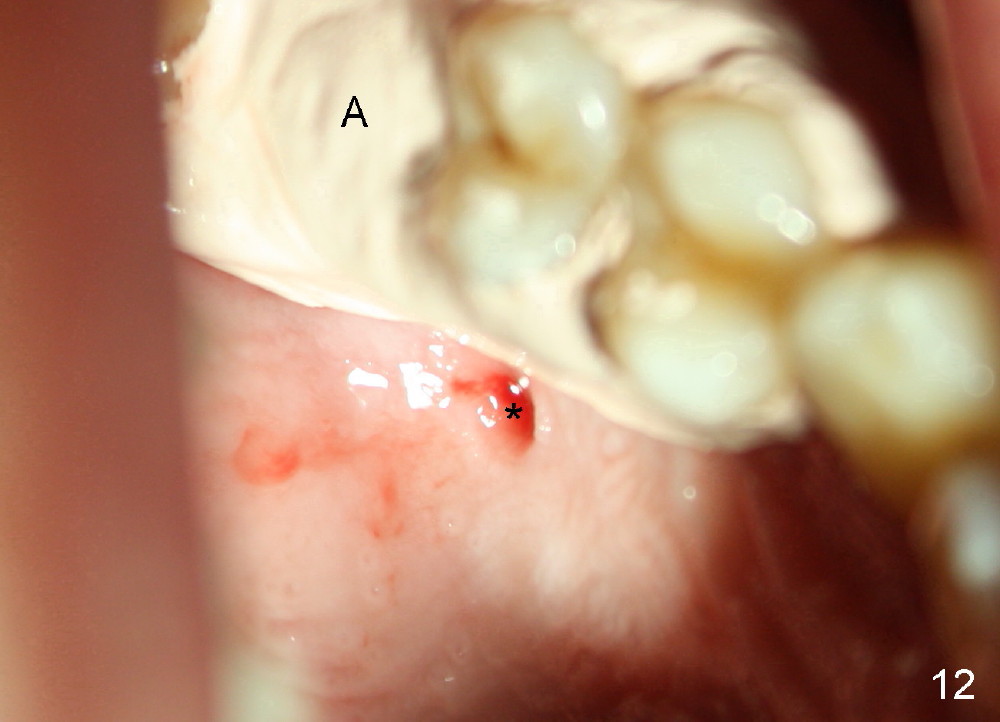

The upper right 1st molar of a 48-year-old man has severe perio endo disease (Fig.1 #3); the bone height for immediate implant (Fig.2) is about 3.5 mm (Fig.1 vertical line). There is a buccal (Fig.3 B) abscess (*); the palatal (Fig.4 P) root is exposed. After extraction, the socket available for immediate implant (Fig.5,6 S) is buccal (without septum), whereas the apex of the palatal root is far away from the main socket. In fact there is an advantage: the socket is smaller. Osteotomy is created in the main socket as palatal as possible, using osteotomes, reamers and taps (Fig.7 T). The sinus floor is lifted (Fig.7 ^). When 7x17 mm implant is placed (Fig.8 I), the insertion torque is >60 Ncm. The remaining socket (Fig.8 *) is to be packed with mixture of autogenous bone, allograft and synthetic bone (Osteogen) (Fig.9,10 <). Immediate insertion of an abutment (Fig.8-10 A) helps retain perio dressing (Fig.11,12). No collagen membrane is used in this case to cover the bone graft before placement of perio dressing. Postop the patient cannot tolerate oral Amoxicillin because of stomach upset. The dose is reduced. Two weeks postop, the perio dressing is stable, but discolors (Fig.13). When the dressing is removed, the buccal bone graft is exposed, which is not abnormal. What is unusual is discoloration (Fig.14). The significance of the latter is not revealed until 3 months postop when the patient remains asymptomatic, but there is an apical fistula (Fig.15 <). There is a communication between the fistula and the buccal sulcus of the implant: water passing freely. Based on the position of the buccal plate of the neighboring teeth (*), the buccal plate of the implant should be lost, which is consistent with finding of PA (Fig.16, as compared to Fig.8). Guided bone regeneration seems necessary.